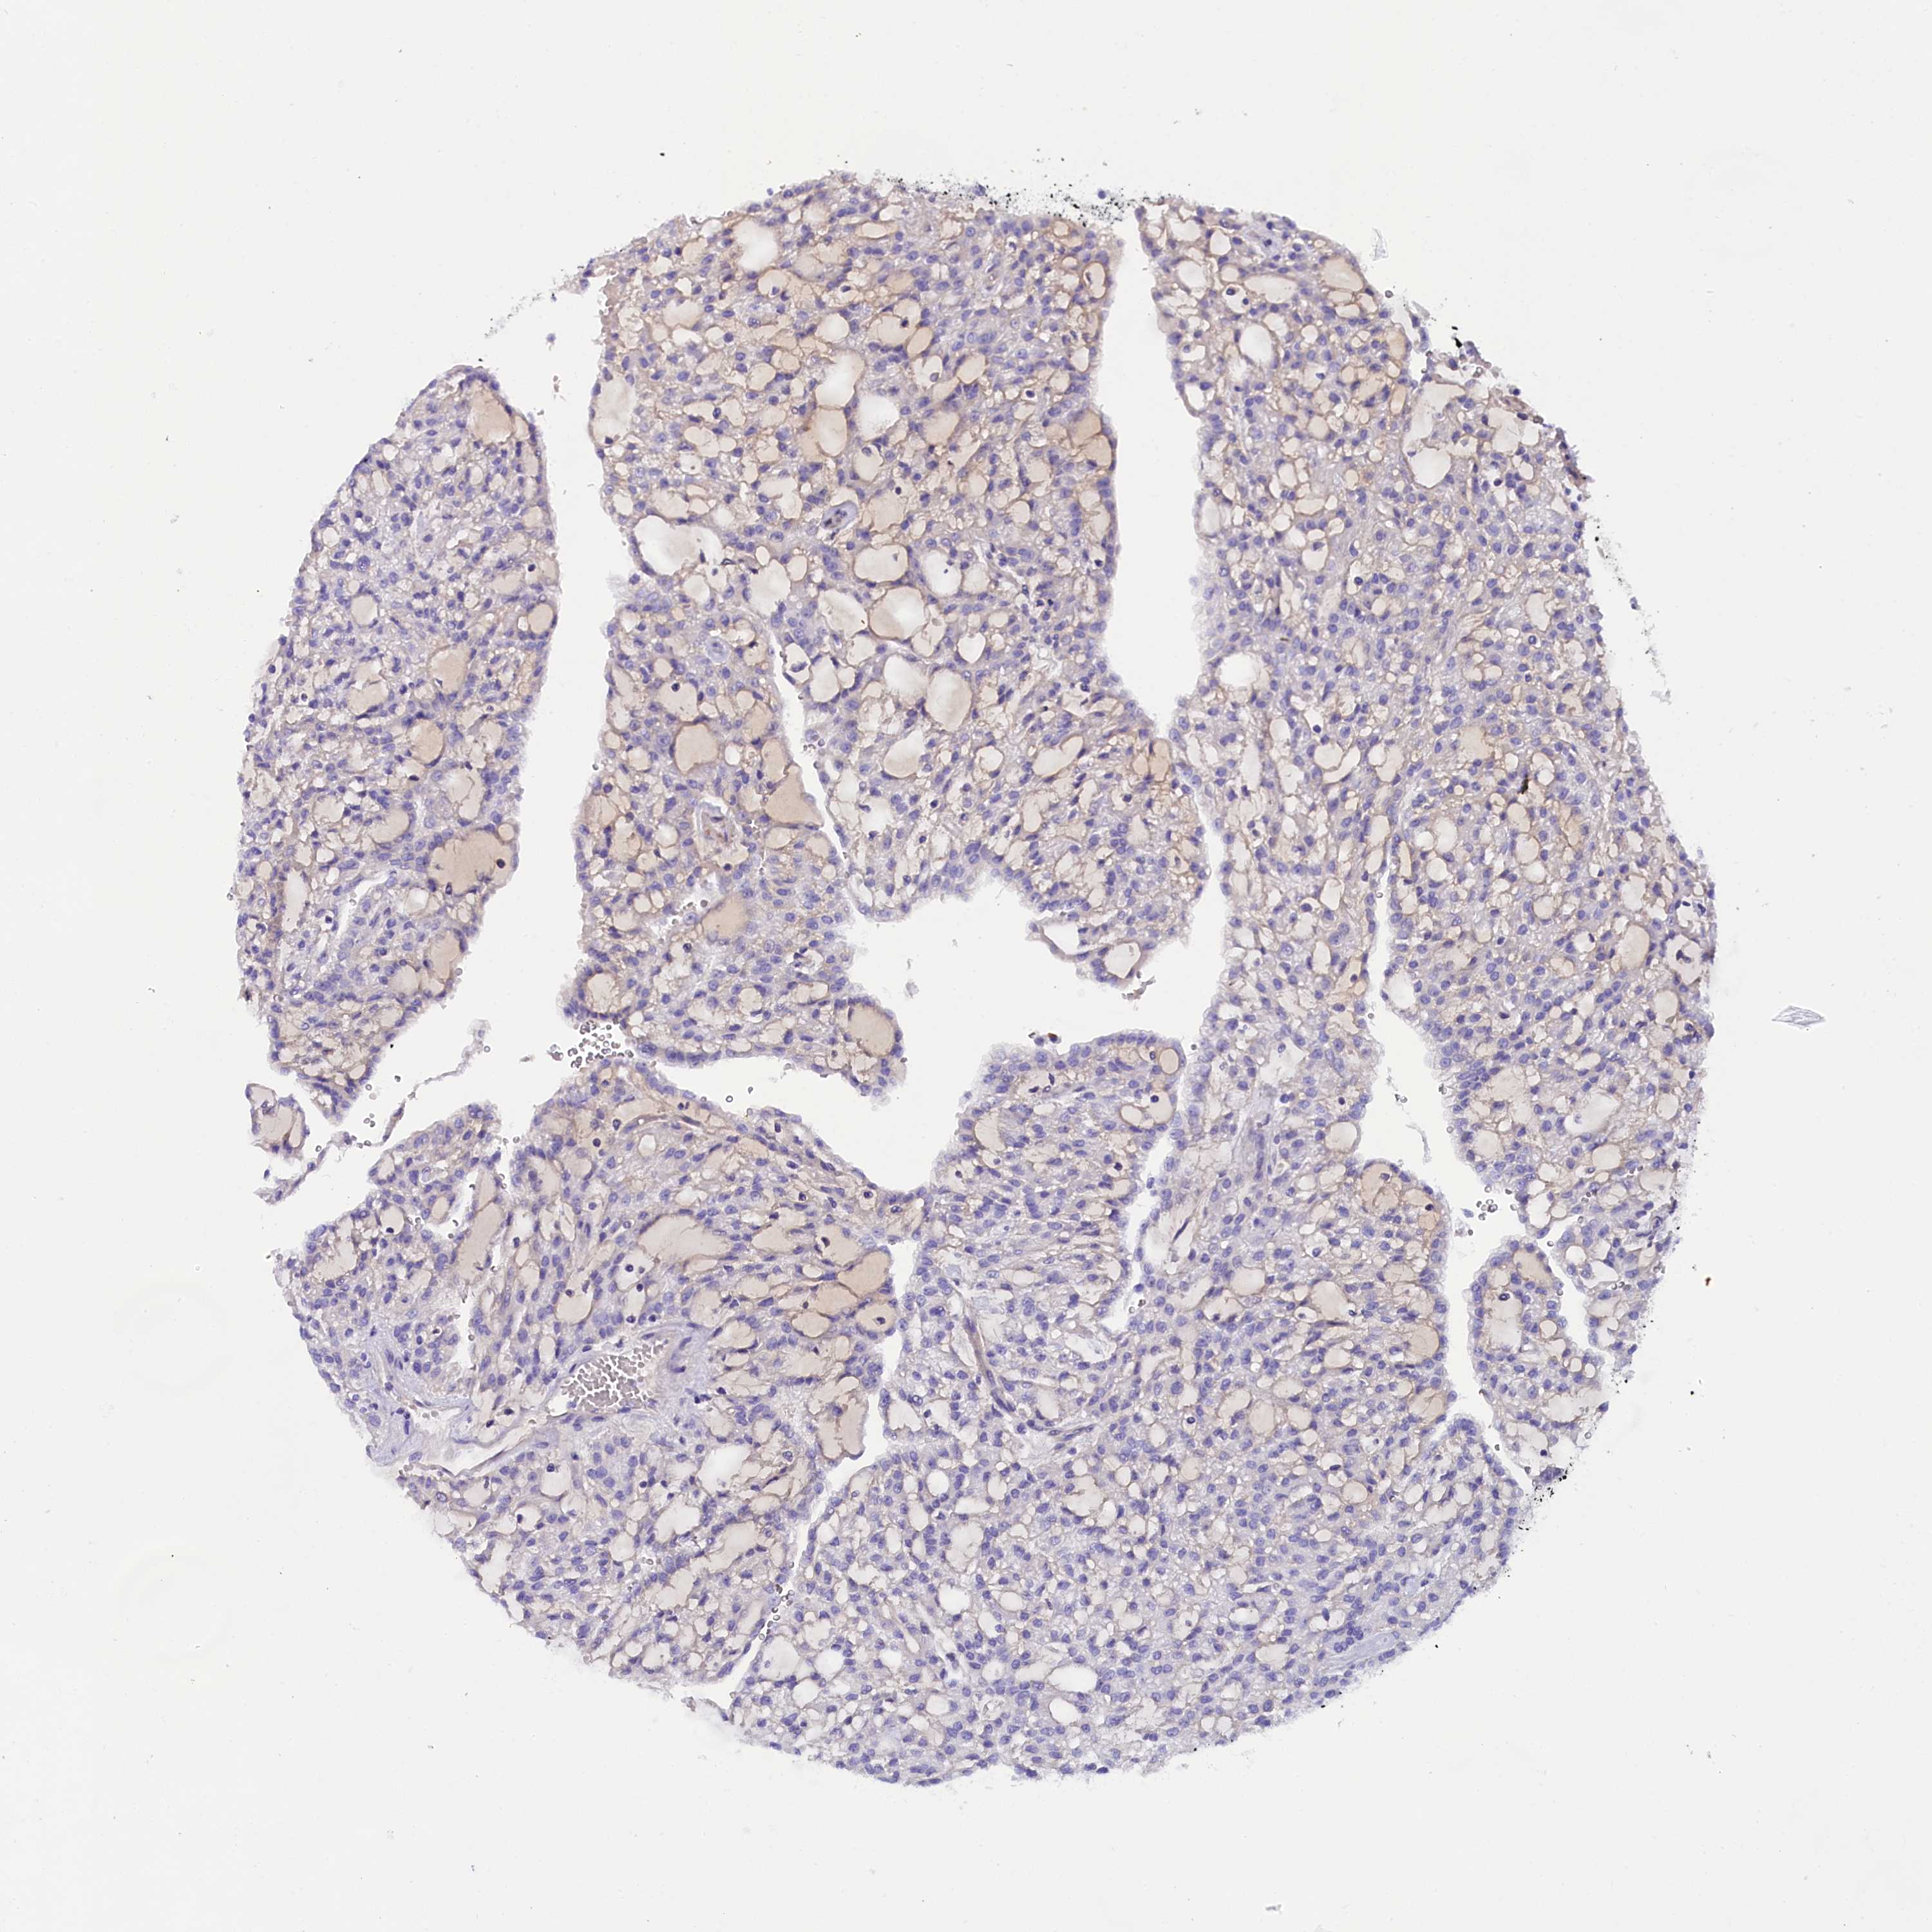

SOD3

CANCER RENAL CANCER Show tissue menu

KICH TCGA KIRC TCGA KIRC VALIDATION KIRP TCGA PROTEIN RCC CPTAC PROTEIN EXPRESSION